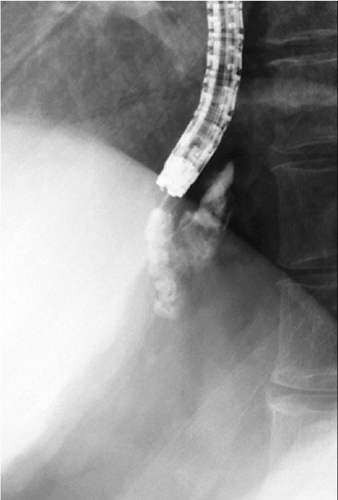

経皮経肝門脈造影

門脈および供血路、食道静脈瘤が描出されている。